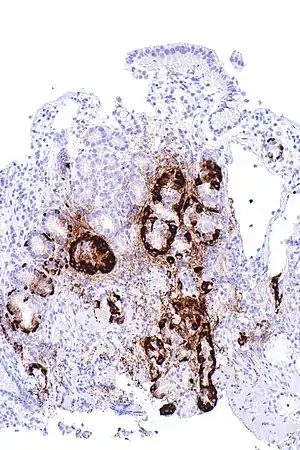

| Micrograph showing nodular enterochromaffin-like cell hyperplasia, as demonstrated with chromogranin A immunostaining, in the body of the stomach. Parietal cells are not readily apparent. These changes are in keeping with autoimmune metaplastic atrophic gastritis, a histologic correlate of vitamin B12 deficiency anemia. | |